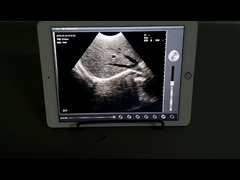

Kwaliteit Draagbare ultrasone Scanner, handbediende Ultrasone klankscanner Fabrikant uit China

Alle video's